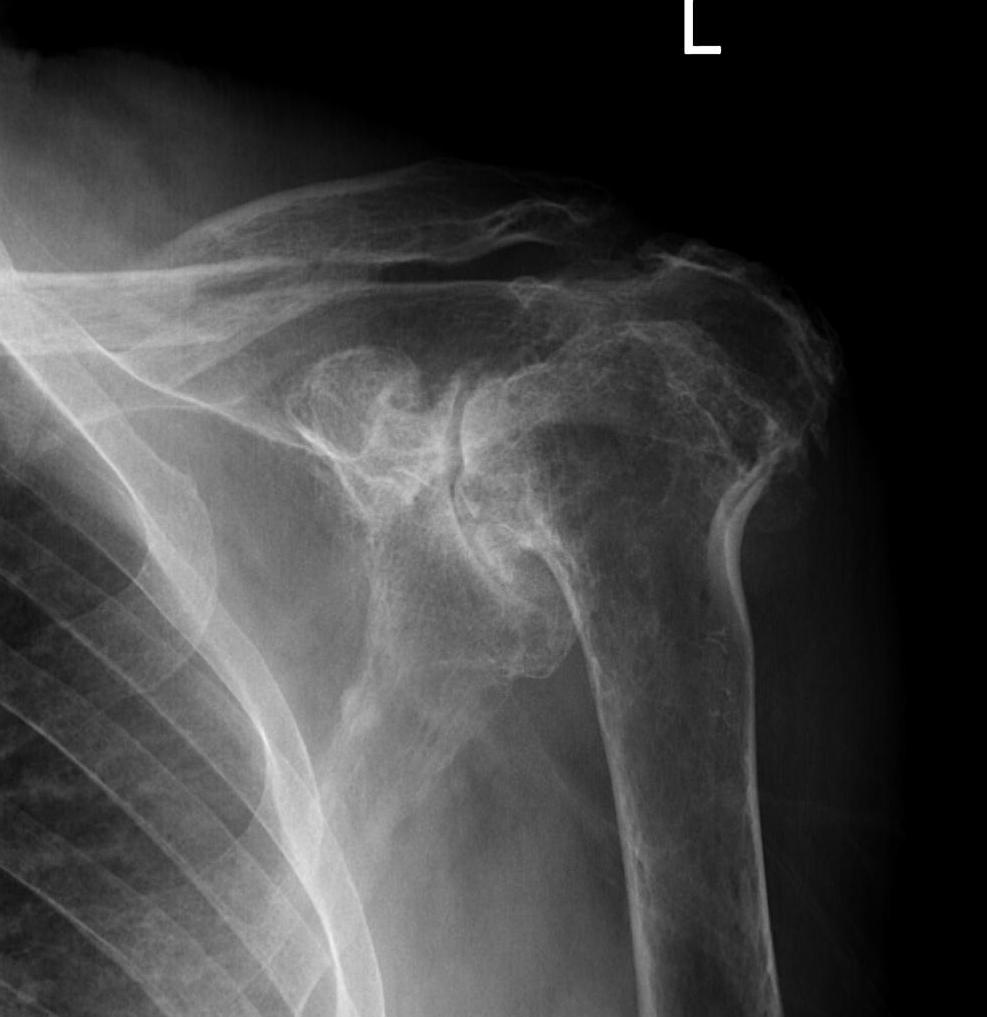

From www.jshoulderelbow.org

The mode of destruction in shoulders with rheumatoid arthritis based on Rheumatoid Arthritis In My Shoulder While the number of people with shoulder problems in the general population is smaller, people with ra will have notable shoulder tenderness and swelling as early as two years after diagnosis. What are the symptoms of ra in the shoulders? Is ra more likely to affect one shoulder or. In some people, the condition can damage. rheumatoid arthritis (ra). Rheumatoid Arthritis In My Shoulder.